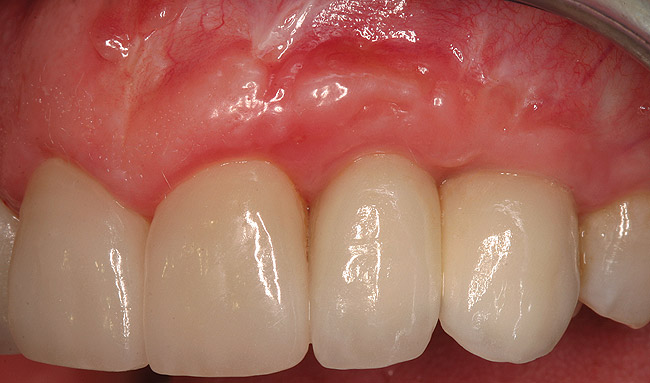

Figure 21  (Case 2) Final implant restoration with adjacent crowns following surgical crown lengthening.

Figure 21

Figure 22  (Case 2) Final smile with anterior restorations in place.

Figure 22